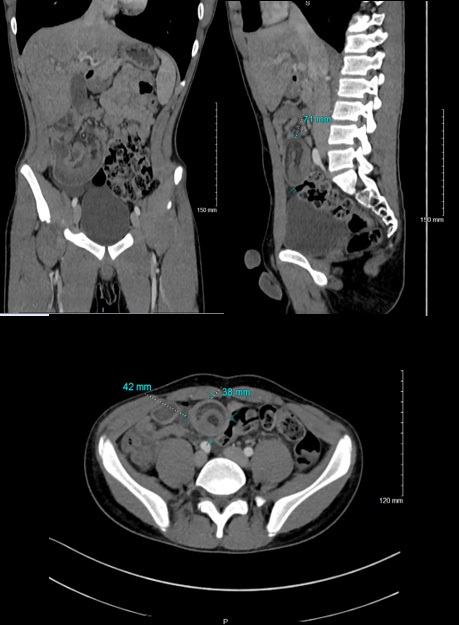

An abdominal computed tomography found the presence of an ileo-ileum intussusception in the right iliac fossa (the sausage 42 x 38 mm in diameter and 71 mm in length) whose content is a fatty image within the infiltration linked to the intussusception of the mesenteric fat, the presence of signs of early intestinal pain. Furthermore, there was no parietal enhancement defect, no identifiable underlying mass syndrome, but the presence of submillimetric nodal formations with the neighboring minor axis (Figure 3).